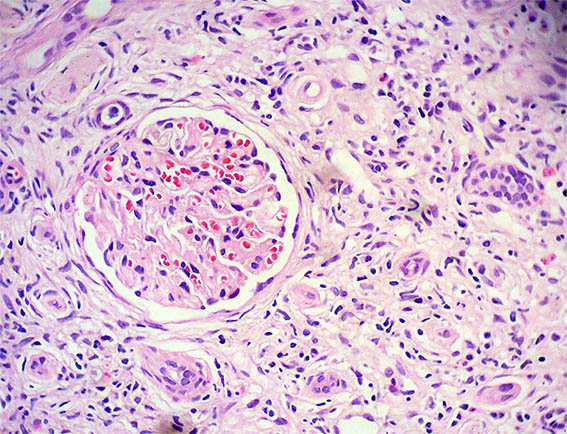

Figura 3.

H&E, X400. Infiltrado intersticial de linfocitos, neutrófilos, eosinófilos y células plasmáticas.